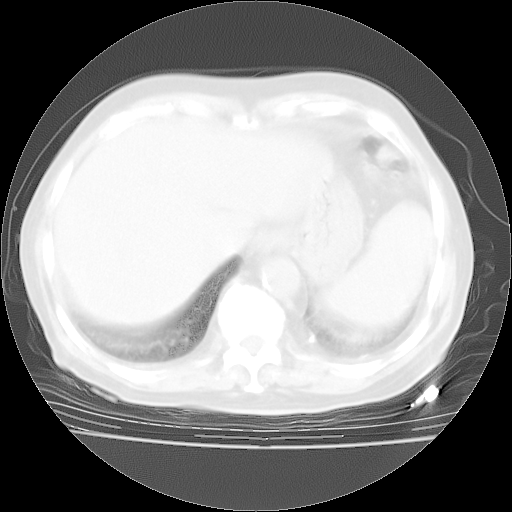

腹部B超:胆囊壁增厚,肝、胆、胰、脾、肾无异常,肠系膜淋巴结、腹膜后淋巴结无增大。